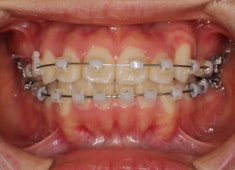

治療開始時